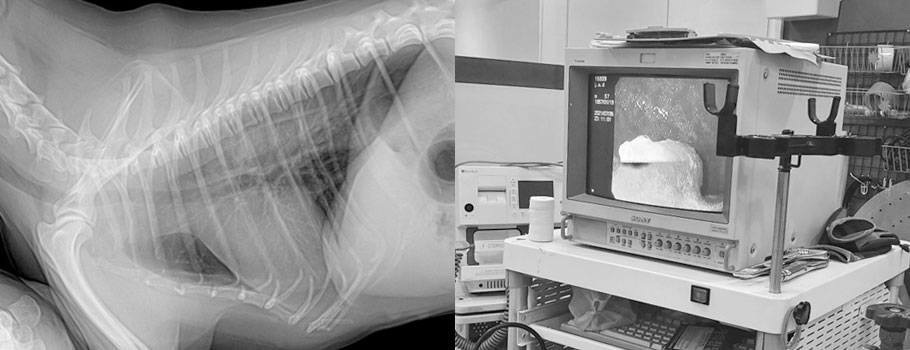

1 소화이물 제거수술

위나 장내에 다양한 이물들을 제거하는 수술입니다.

2 내시경

소화기내 다양한 이물을 수술이 아닌 내시경으로 제거합니다.